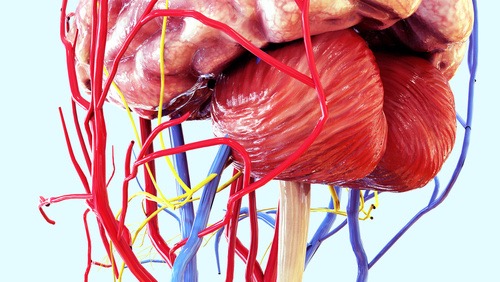

痛みの原因が見つかったらいよいよ治療を行います。このセッションでは筋膜だけでは治せない腰痛治療に必須のFCRメソッドをお伝えします。内蔵、神経、血管等に対するFCRメソッドの有効性と効果の高さをその身をもって体感して下さい。このセッションを受けることであなたは、、、